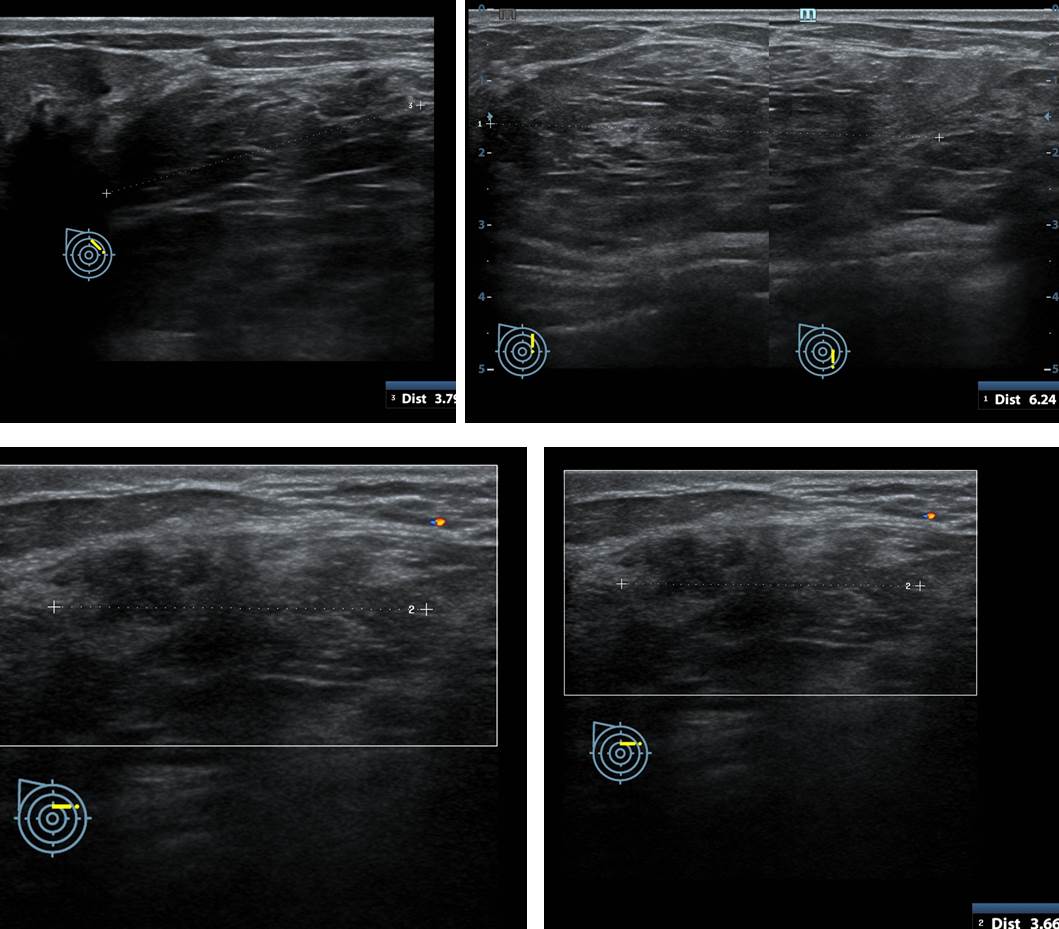

From www.semanticscholar.org

Figure 2 from Imaging features of triple negative breast carcinoma mammography, ultrasound and Painful Breast Lump Radiology Most palpable breast lumps are benign. Palable breast masses are common and usually benign, but efficient evaluation and prompt diagnosis are necessary to rule out. Breast ultrasound should be the primary imaging tool for women with palpable lumps who are pregnant, lactating, or younger than 30 years. Do breast cancer lumps ever hurt? Most breast cancers don’t cause any pain,. Painful Breast Lump Radiology.